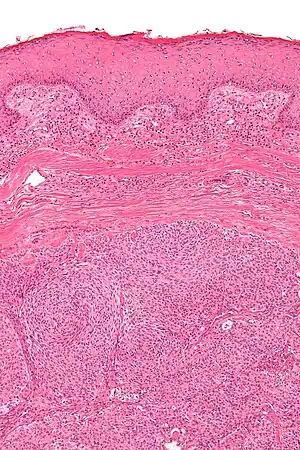

| Micrograph showing an acrospiroma. H&E stain. | |

Hidradenoma refers to a benign adnexal tumor of the apical sweat gland.[1][2] These are 1–3 cm translucent blue cystic nodules. It usually presents as a single, small skin-colored lesion, and may be considered closely related to or a variant of poromas.[3] Hidradenomas are often sub-classified based on subtle histologic differences, for example:[4]